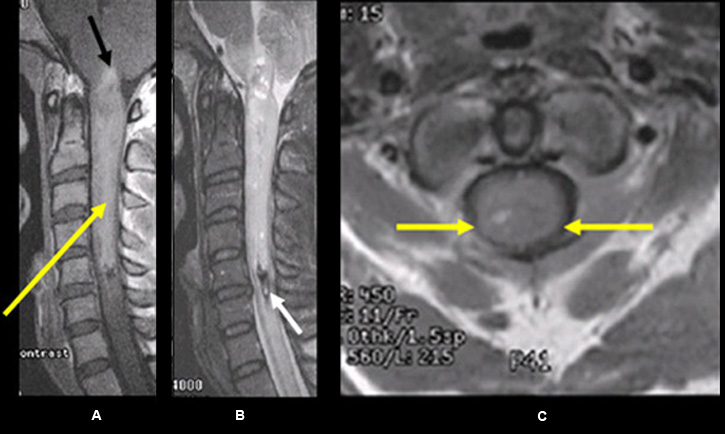

Imaging findings: Figure 2

- Pre-contrast sagittal T1wtd. MRI of the lumbar spine

- bony metastasis (yellow arrow) is seen involving the T12 vertebral body

- Post-contrast (C+) sagittal T1wtd. MRI

- yellow arrow points to the bony metastasis that enhances with contrast

- red arrow points to intramedullay location of metastasis within the distal thoracic cord and showing contrast enhancement

- Sagittal T2 wtd. MRI

- green arrow points to edema within the thoracic cord

- Post-contrast (C+) axial T1wtd. MRI

- red arrow points to intramedullary metastasis

Findings are consistent with vertebral body metastasis and intramedullary metastasis from renal cell carcinoma. |